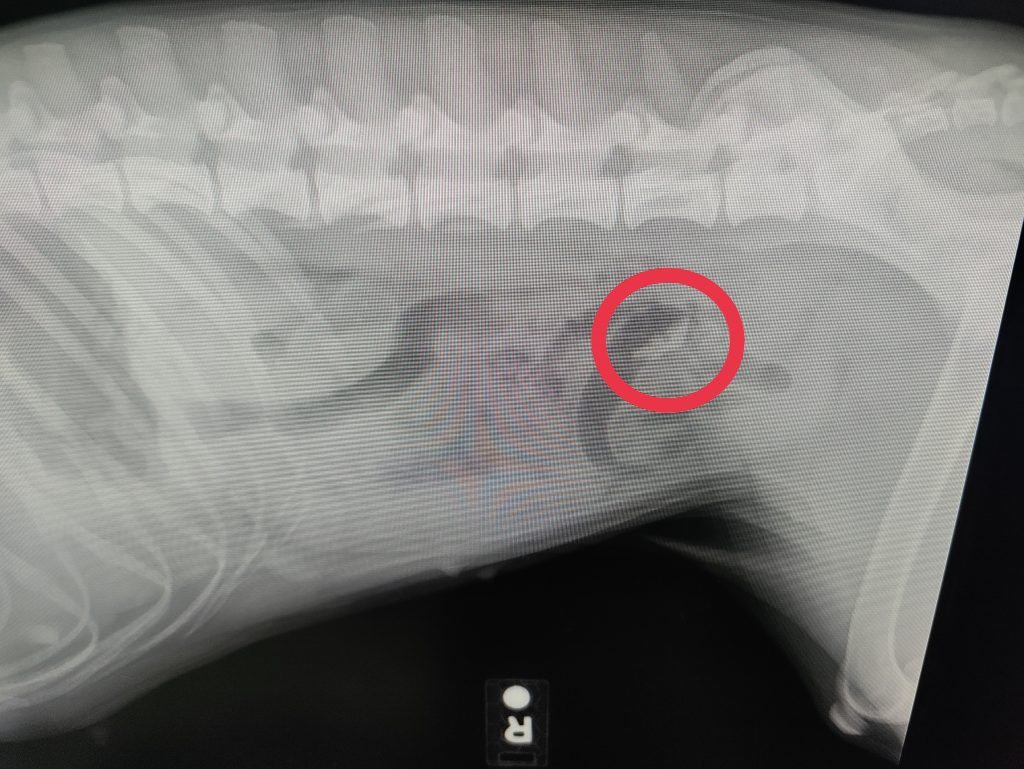

She ate something, I suspect the squeaker from a toy recently destroyed, and it blocked up her insides. So she vomited a bunch of thick yellow bile and I took her to the vet.

First visit we didn’t get great news. They wanted to hospitalize her ($$) and then possibly operate on her ($$$). But they sent us home after injecting a bunch of water into her skin. That was wild but it helped move this squeaker down the line. We laid on the couch for the rest of the day and night and went for another x-ray in the morning.

Second visit was about 16 hours after the first. Way better news this time. Whatever that was blocked has broken up considerably and is moving. So good news, go home, drop a deuce and eat up.